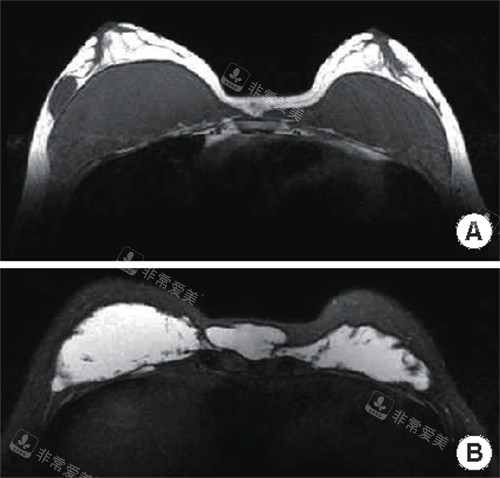

不明注射物在胸部的样子